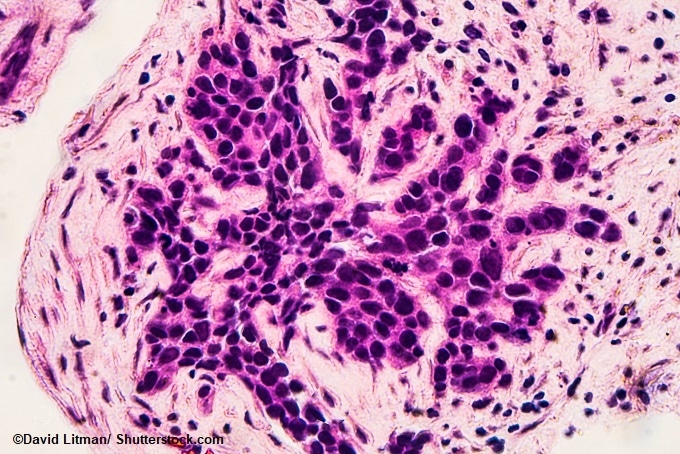

Image: Photomicrograph of core biopsy for infiltrating (invasive) ductal carcinoma, detected by screening mammogram. H & E stain.

Tissue samples from 1,178 women who were affected with estrogen receptor positive breast cancer – the most common type of breast cancer –were analyzed in the study. These samples were obtained as a part of a clinical trial done at The Royal Marsden NHS Foundation Trust that compared two hormone therapies which has the capability to prevent cancer from relapsing after the surgery. In order to analyze these samples, the team developed a new, completely automated computer tool.